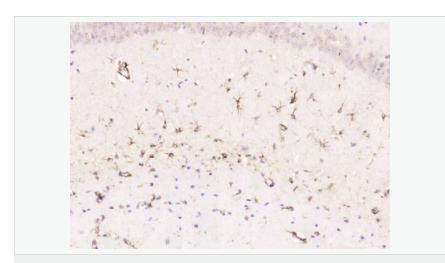

| 產品應用 | WB=1:500-2000 ELISA=1:5000-10000 IHC-P=1:200-1000 IHC-F=1:200-1000 Flow-Cyt=1μg/Test ICC=1:100 IF=1:200-800 (石蠟切片需做抗原修復) not yet tested in other applications. optimal dilutions/concentrations should be determined by the end user. |

| 產品介紹 | This gene encodes one of the major intermediate filament proteins of mature astrocytes. It is used as a marker to distinguish astrocytes from other glial cells during development. Mutations in this gene cause Alexander disease, a rare disorder of astrocytes in the central nervous system. Alternative splicing results in multiple transcript variants encoding distinct isoforms. [provided by RefSeq, Oct 2008] Function: GFAP, a class-III intermediate filament, is a cell-specific marker that, during the development of the central nervous system, distinguishes astrocytes from other glial cells. Subunit: Interacts with SYNM. Isoform 3 interacts with PSEN1 (via N-terminus). Subcellular Location: Cytoplasm. Note=Associated with intermediate filaments. Tissue Specificity: Expressed in cells lacking fibronectin. Post-translational modifications: Phosphorylated by PKN1. DISEASE: Defects in GFAP are a cause of Alexander disease (ALEXD) [MIM:203450]. Alexander disease is a rare disorder of the central nervous system. It is a progressive leukoencephalopathy whose hallmark is the widespread accumulation of Rosenthal fibers which are cytoplasmic inclusions in astrocytes. The most common form affects infants and young children, and is characterized by progressive failure of central myelination, usually leading to death usually within the first decade. Infants with Alexander disease develop a leukoencephalopathy with macrocephaly, seizures, and psychomotor retardation. Patients with juvenile or adult forms typically experience ataxia, bulbar signs and spasticity, and a more slowly progressive course. Similarity: Belongs to the intermediate filament family. SWISS: P14136 Gene ID: 2670 Database links: Entrez Gene: 2670 Human Entrez Gene: 14580 Mouse Omim: 137780 Human SwissProt: P14136 Human SwissProt: P03995 Mouse Important Note: This product as supplied is intended for research use only, not for use in human, therapeutic or diagnostic applications. 星形膠質細胞標志物 (Astrocyte Marker) GFAP是一個56kDa的中間絲蛋白(intermediate filament,IF),在中樞神經系統(tǒng)發(fā)育期是一個特異性的標志物,以區(qū)別星形細胞和其它膠質細胞。GFAP表達在皮層和海馬,急、慢性皮質酮治療時表達減少。 GFAP可以和人、大鼠、小鼠的GFAP反應,在正常和腫瘤性的星形膠質細胞陽性表達,而神經節(jié)細胞、神經元、成纖維細胞、少突膠質細胞和這些細胞來源的腫瘤細胞陰性表達,主要用于星形膠質瘤等中樞神經系統(tǒng)腫瘤的診斷和鑒別診斷,GFAP的缺乏可導致AD病。 |